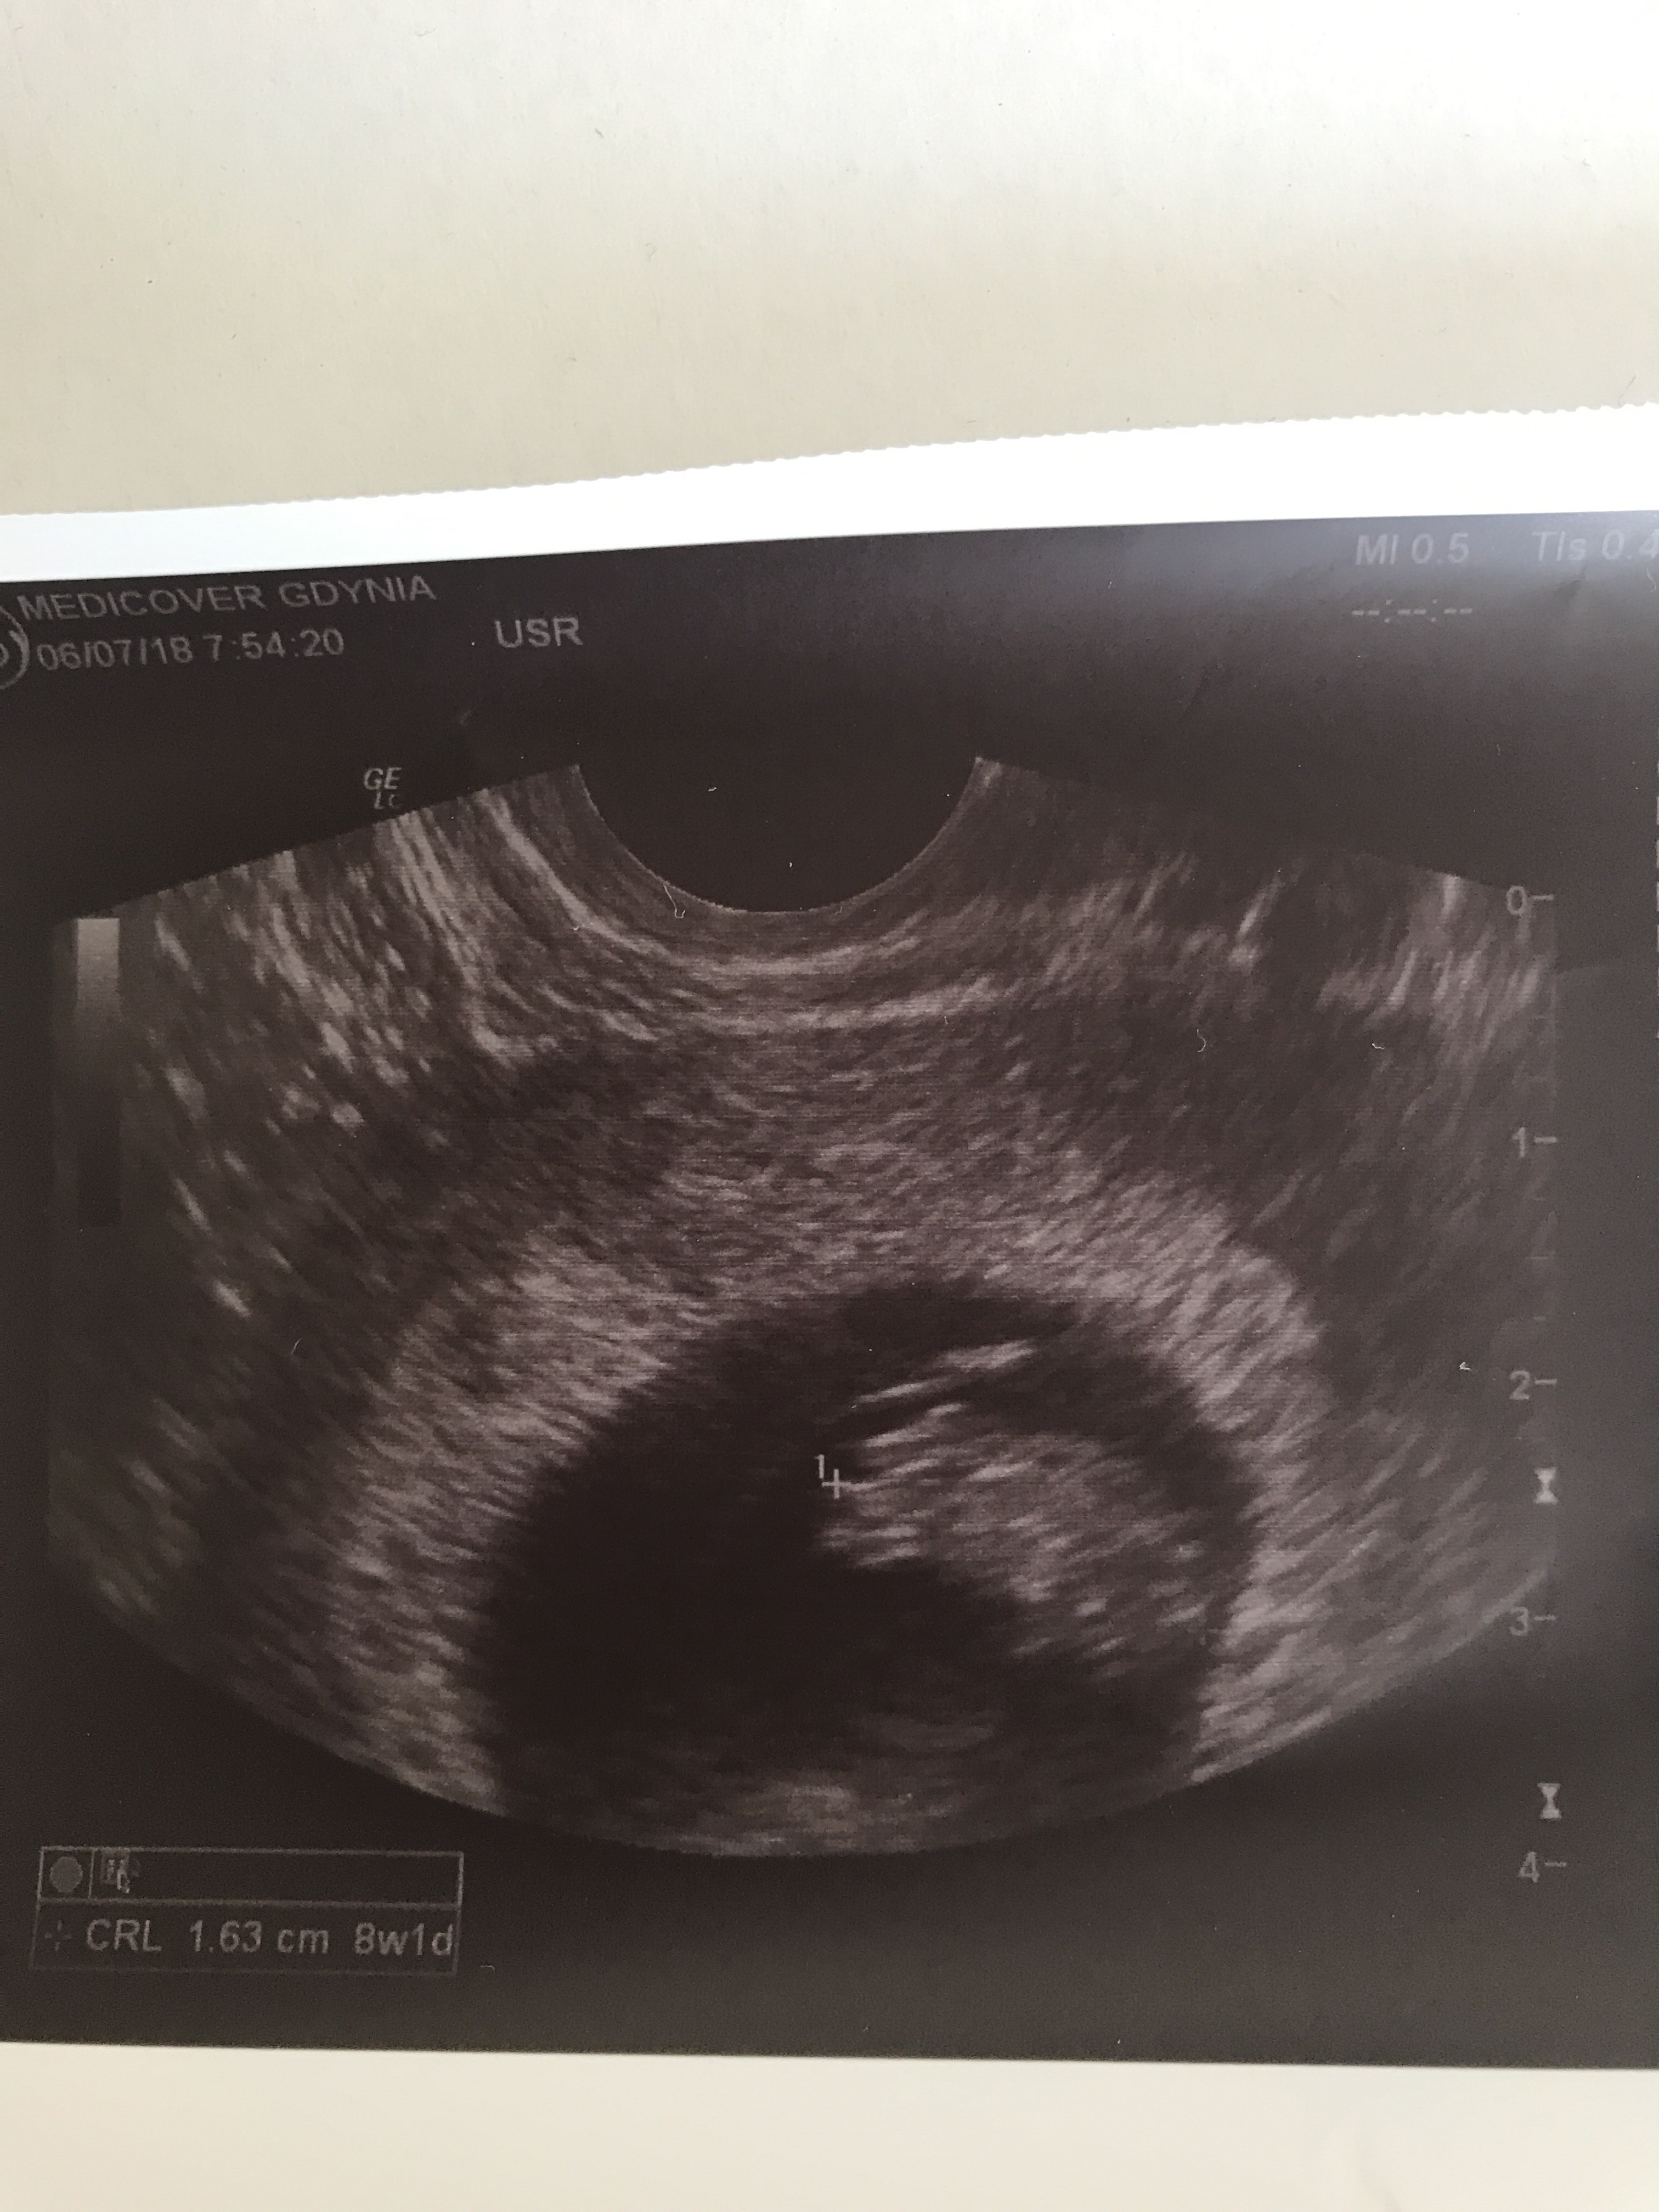

Hej Kochane, ja dzisiaj miałam nieplanowaną wizytę u ginekologa... W środę popołudniu delikatnie plamiłam, ale wczoraj w ciągu dnia nic już nie było i czułam się bardzo dobrze. Dopiero wieczorem znowu zaczęłam plamić, ale już mocniej i śluz był bardziej czerwony. Całą noc to samo, już byłam załamana. Rano dostałam się do ginekologa i po badaniu stwierdził ze nie ma nowego źródła krwawienia, ale są ślady po starym i teraz mam leżeć i odpoczywać. Mieliśmy jechać na weekend do Krakowa, a później na tydzień w Bieszczady, ale lekarz zabronił, a wiec czeka mnie tydzień urlopu w łóżku ;-) Zabronione też współżycie. Na szczęście fasolka żyje :-) urosła 1 cm od 26.06 :-) i na zdjęciu przypomina królika ;-)Zobacz załącznik 874428

Jak na razie wszystko wygląda dobrze, wczoraj mieliśmy wizytę i jak się okazało nasz Maluch już nie jest taki mały bo ma 8 tyg i 3 dni i pięknie bijące serduszko. :)